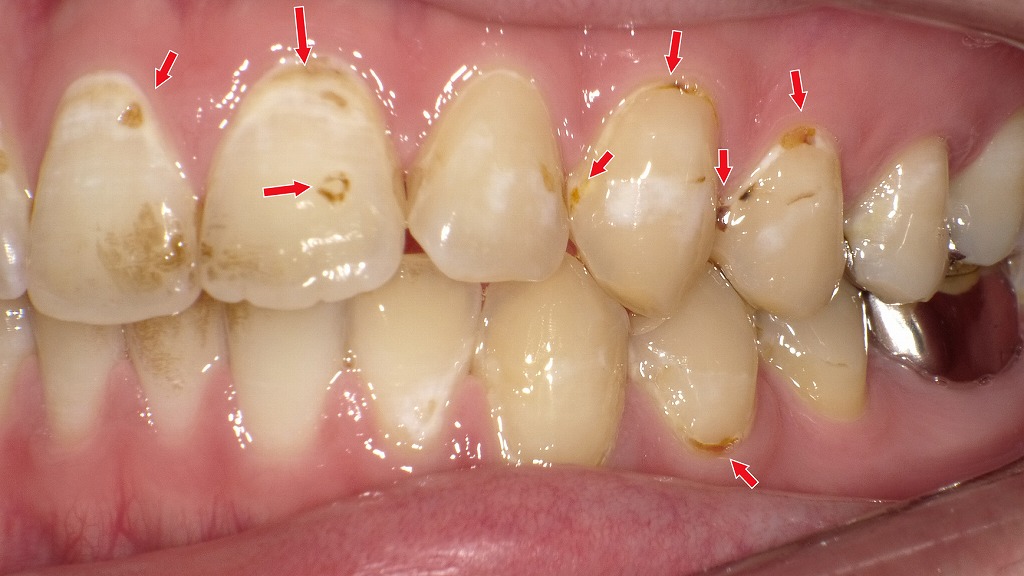

赤矢印が示すように、歯と歯の間(コンタクト部)の初期虫歯は、肉眼ではほとんど確認できません。レントゲンを撮影することで、エナメル質内部の透過像として虫歯を早期に発見できます。見た目に穴がなくても進行している場合があるため、定期的なレントゲン検査は非常に有効です。